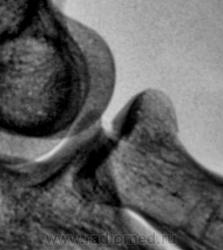

Боковая проекция.

Фрагменты с увеличением.

Предположу продольный перелом головки луча с допустимым смещением.